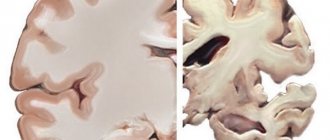

Причины Точных причин, приводящих к развитию нейродегенеративных заболеваний головного мозга, в настоящее время не